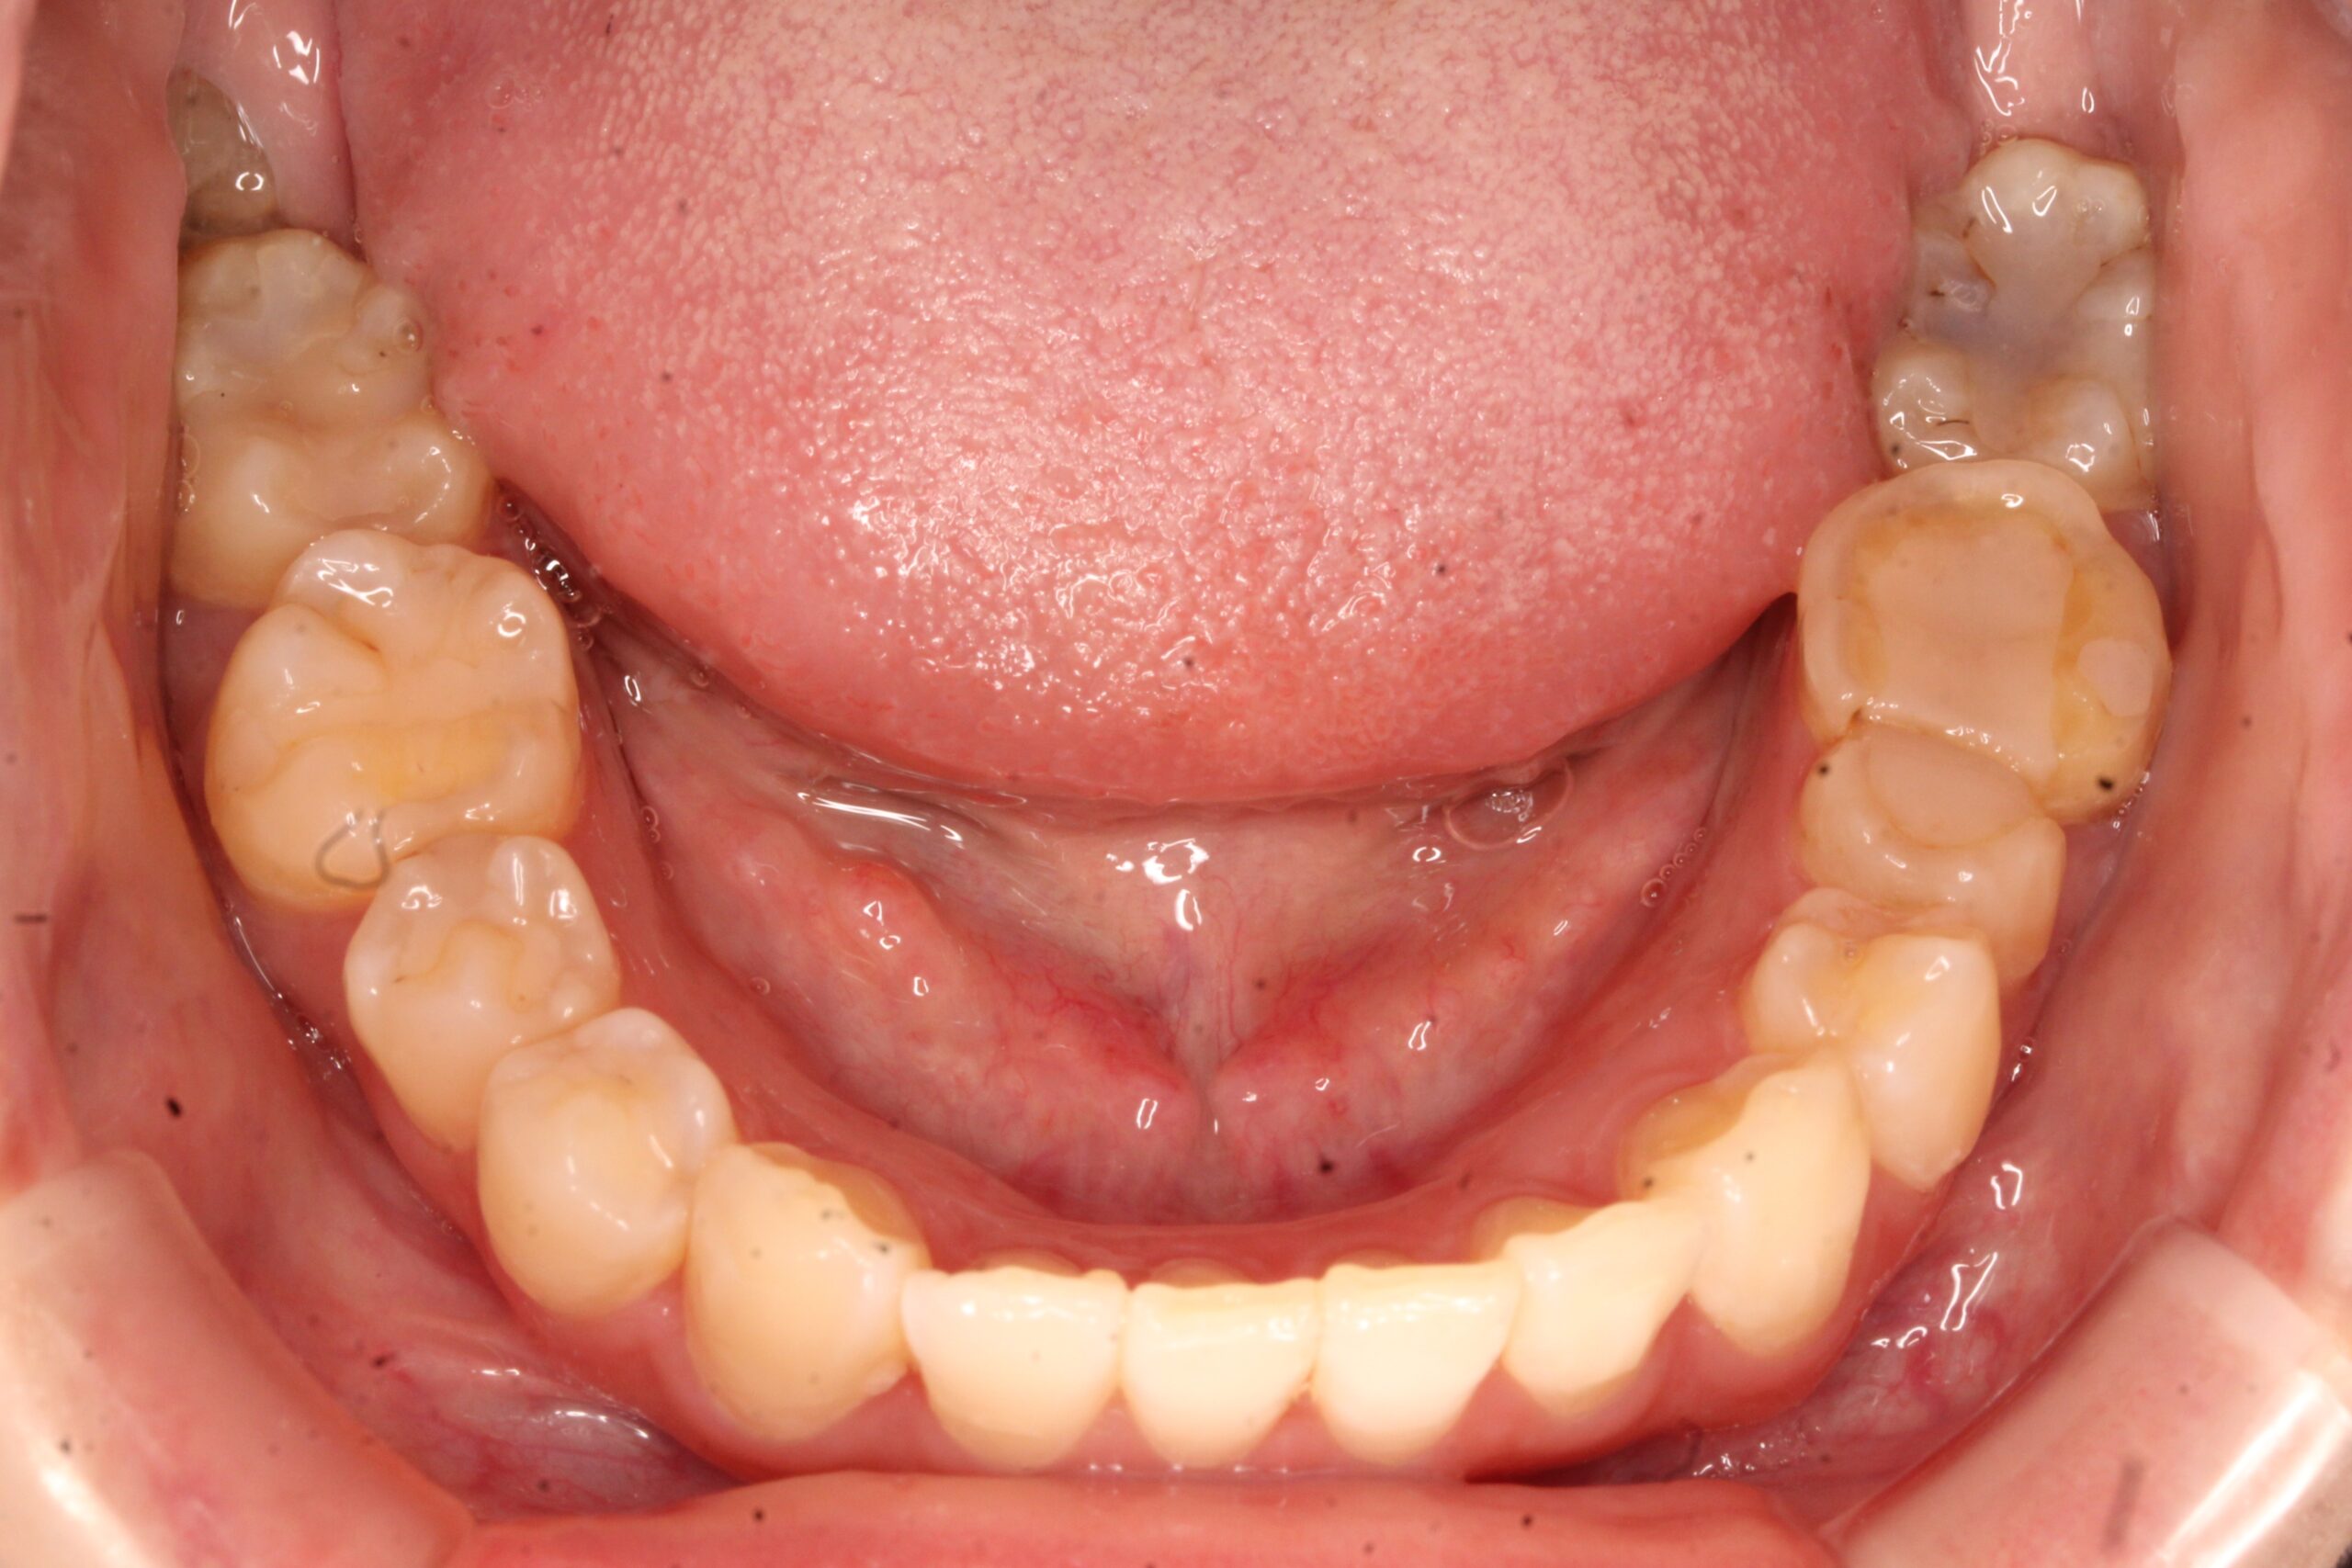

矯正術前:下顎

矯正術後:下顎